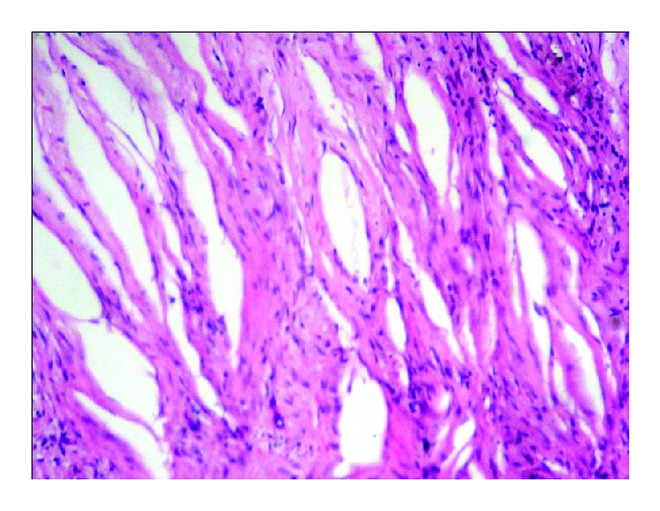

CG histopathologically depicts a large collection of longitudinal cholesterol clefts that are formed at the site of cholesterol crystals because of dissolution of crystals at the time of tissue processing and is embedded in fibrous granulation tissue with surrounding foreign body type of multinucleated giant cells and macrophages filled with hemosiderin [4]. After an extensive survey, six cases of CG have been found in the oral cavity, in which only three cases of CG occurring in the wall of odontogenic cyst have been reported so far [3–7]. We report additional three cases of CG occurring in wall of odontogenic cysts (Table 1).

CG could lead to expansion of the lesion with which it is associated. Almada et al. [10] reported that there are chances of primarily or secondarily inflamed odontogenic lesions that exhibit foreign body reaction to cholesterol crystals in their capsule and could extend to maxillary sinuses due to anatomical continuity. Yamazaki et al. [9] reported that CG seems to be one of the driving forces for growth of jaw cysts, especially those with inflammatory background. They suggested that low density lipoprotein entrapped by perlecan is accumulated and oxidized in the extracellular space and that oxidized-low density lipoprotein is scavenged by macrophages and is primarily deposited intracellularly; then the macrophages are converted into lipid-laden foamy cells. These foamy cells may originally rupture and release lipids concentrated in their cytoplasm into the extracellular space. Following this, concentrated free cholesterol results in crystallization. Cholesterol crystals in turn cause foreign body reactions to extend inflammatory reactions for cystic growth. Bone erosion may be seen in cholesterol granuloma showing expansive growth [1]. Nair PN et al. stated that macrophages change the hydrophobic cholesterol crystals into a soluble form by incorporating it into lipoprotein vehicle. However, the large cholesterol crystals resist internalization by macrophages and circumfuse to form multinucleated giant cells. Although they persist for prolonged periods, the phagocytes failed to degrade cholesterol and release inflammatory and bone resorptive mediators that cause further loss of bone and extension of lesion [6].